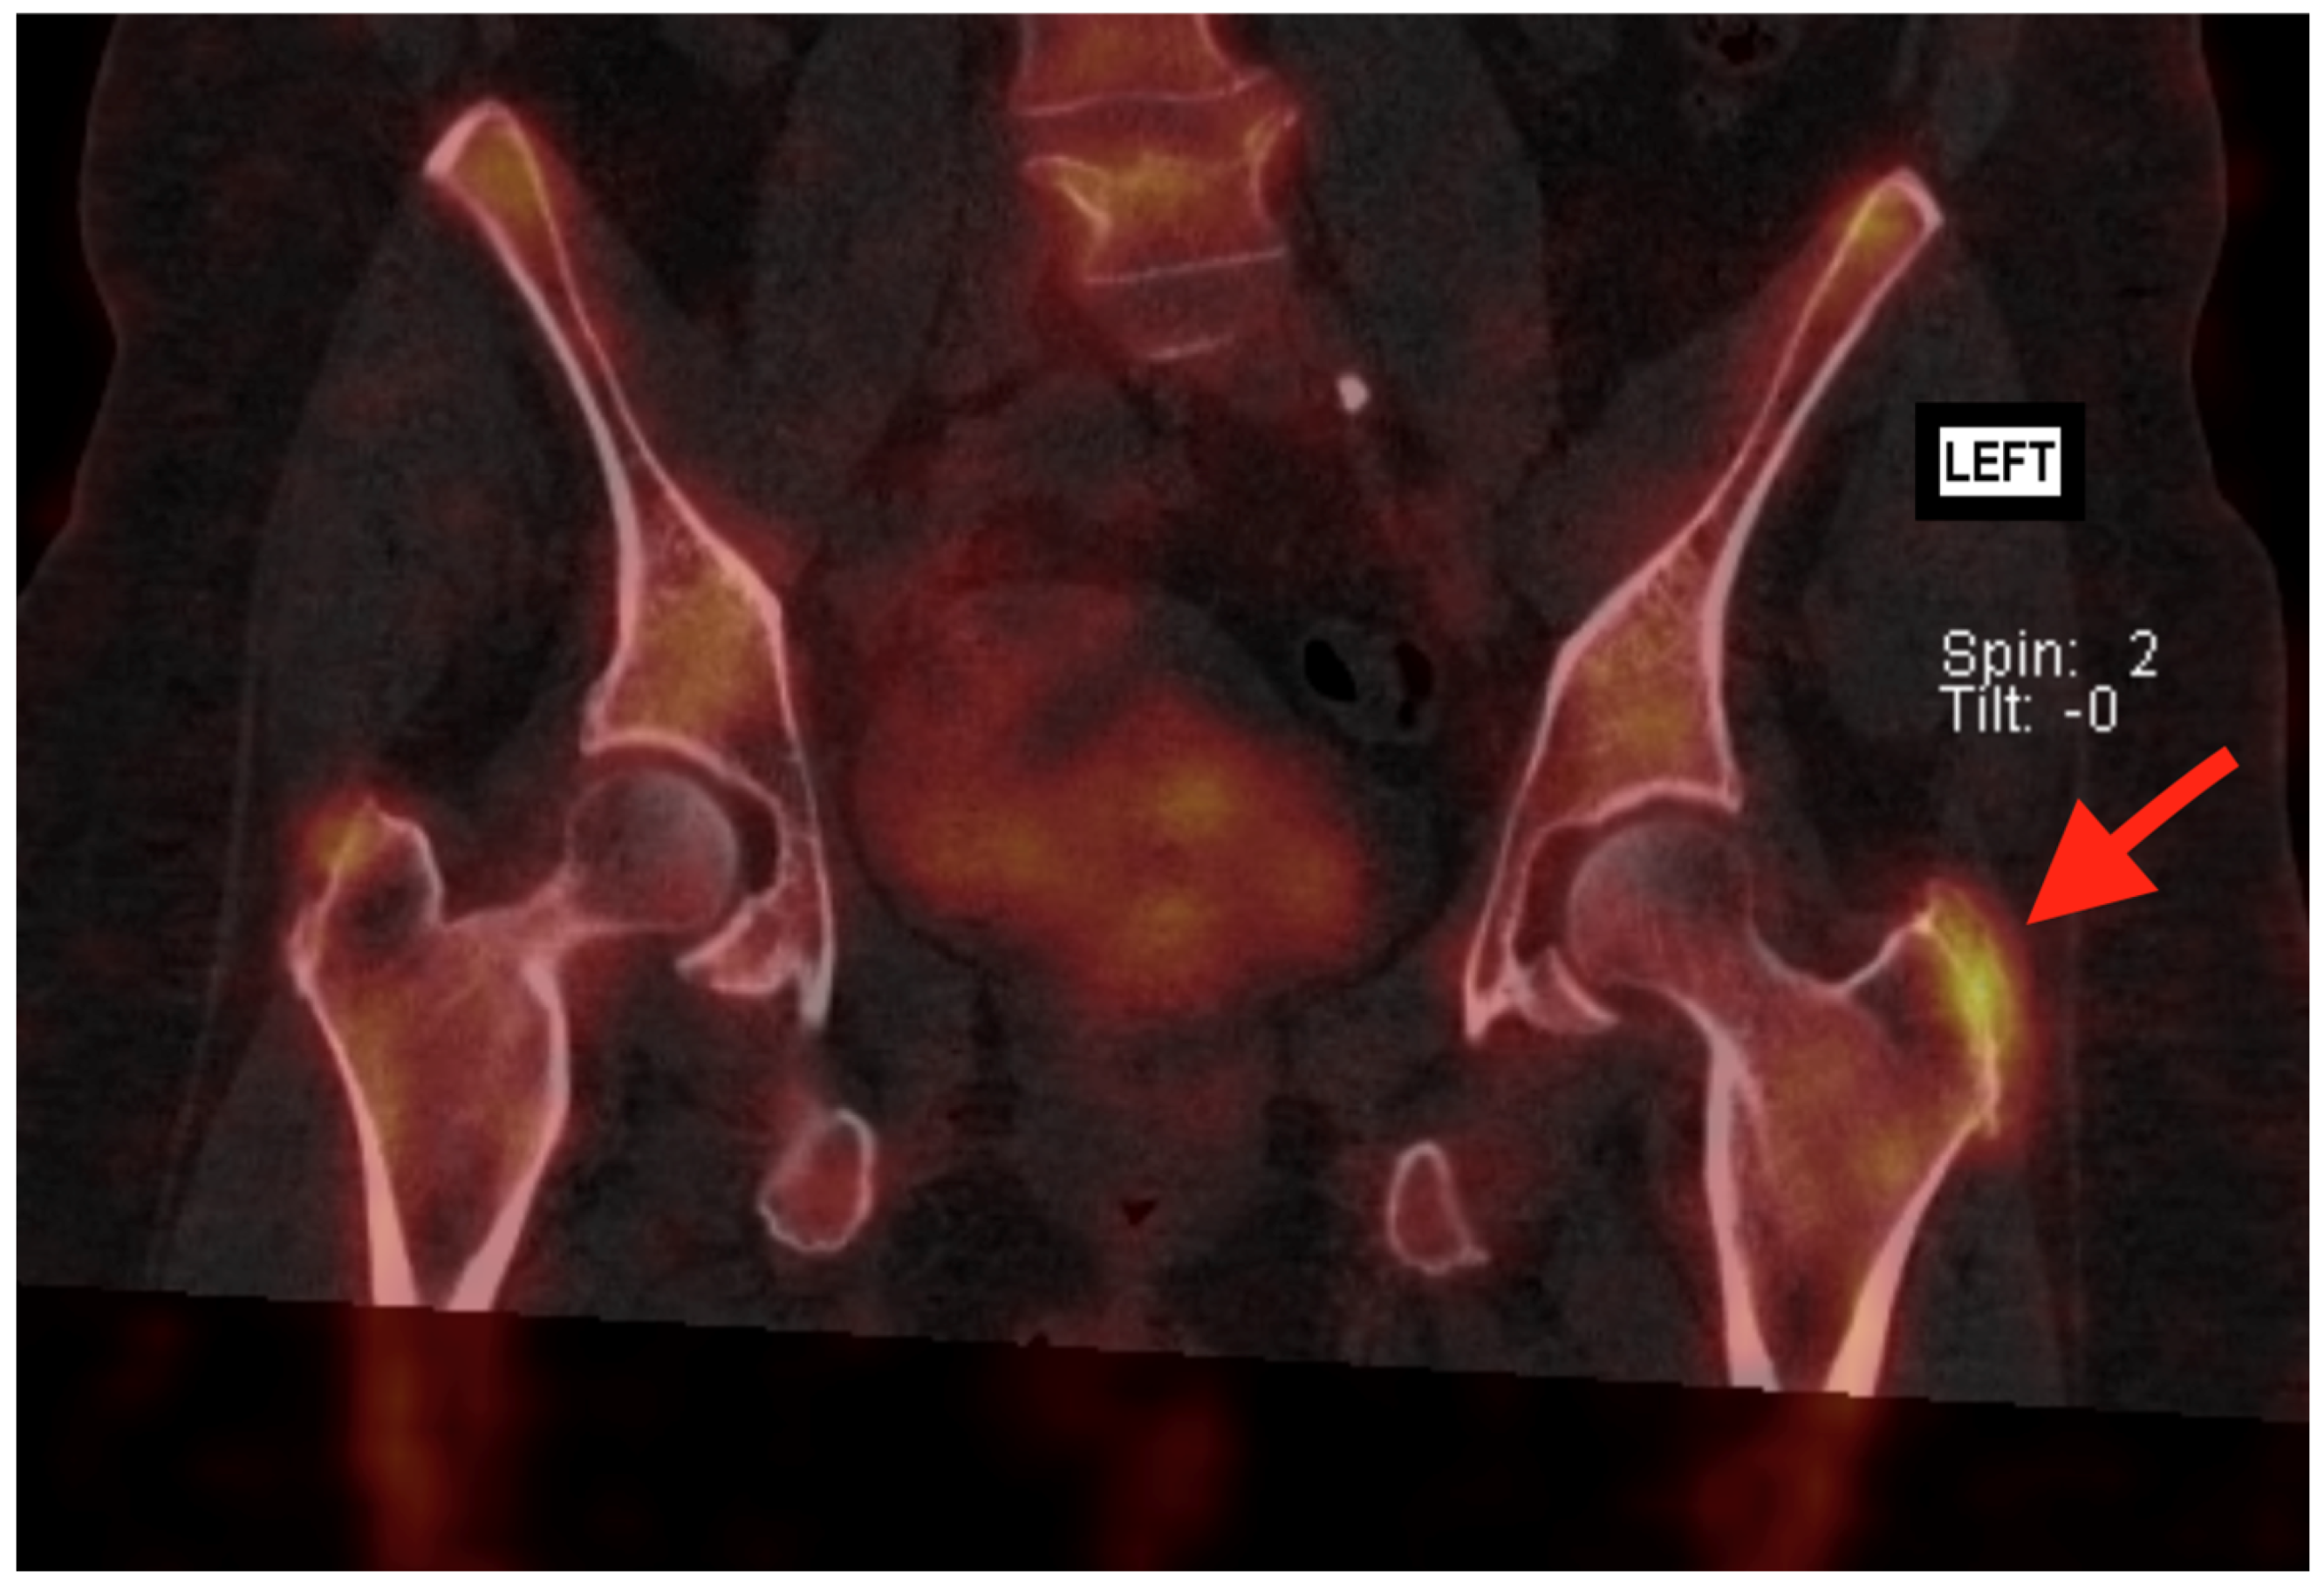

3.4. Bone Scan—SPECT/CT